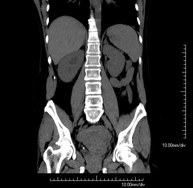

- Abdominal aorta CT angiography

A non-invasive diagnostic test that involves studying the abdominal aorta by obtaining high-definition anatomical images using CT (computed tomography) equipment and iodinated contrast. With the aid of workstations specialised for arterial studies, the image quality supports 2D and 3D reconstructions. It is indicated in patients with vascular disease (atherosclerosis), aortic aneurysms, abdominal pain of possible vascular origin, pre-surgical studies of lesions adjacent to the abdominal aorta as a vascular ‘map’, etc. Information obtained non-invasively is indispensable for patients requiring percutaneous or surgical processing. In patients who only require tracking of vascular lesions, this technique is the non-invasive technique of choice, together with MRI angiography.

- Renal artery CT angiography

A non-invasive diagnostic test that involves studying the renal arteries by obtaining high-definition anatomical images using CT (computed tomography) equipment and iodinated contrast. With the aid of workstations specialised for arterial studies, the image quality supports 2D and 3D reconstructions. This test is recommended, for example, in patients suffering from refractory hypertension that does not respond to processing, in patients with kidney damage in order to obtain a pre-surgical ‘vascular’ map, etc.

- Aortoiliac CT angiography

A non-invasive diagnostic test that involves examining the iliac arteries and abdominal aorta, obtaining high-definition anatomical images using CT (computed tomography) equipment and iodinated contrast dye. With the aid of workstations specialised for arterial studies, the image quality supports 2D and 3D reconstructions. This test is particularly recommended as a pre-surgical study (vascular map) prior to percutaneous or surgical interventions on the abdominal aorta, as a complementary study in patients with lower limb ischaemia, etc.